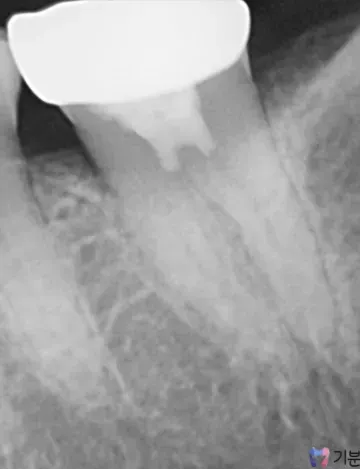

MTA 적용 및 안정적 밀봉

레진 빌드업/인레이/오버레이 등 최종 수복으로 보강

경과 확인(필요 시 추적 관찰)